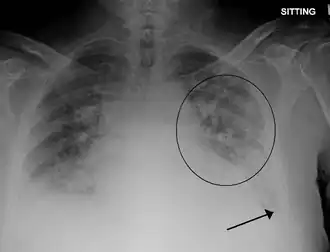

Longoedeem is een schadelijke vochtophoping in de longen, en ontstaat wanneer de bloedvaten in de long beschadigd worden. Daardoor kan vocht uittreden dat zich verspreidt in het interstitium; het weefsel tussen bloedvaten en longblaasjes (alveoli). De zwelling van het interstitium maakt de afstand tussen de longblaasjes en bloedvaten groter waardoor de uitwisseling van zuurstof (longblaasjes → bloed) en koolstofdioxide (bloed → longblaasjes) wordt bemoeilijkt. De normale ademhaling wordt daardoor (ernstig) verstoord waardoor het zuurstofgehalte in het bloed daalt en het koolzuurgehalte in het bloed stijgt. In het ergste stadium van longoedeem kan het vocht ook in de alveoli binnendringen. Uiteindelijk kan de dood intreden.

Acuut longoedeem veroorzaakt kortademigheid en ademhalingsproblemen. De patiënt moet soms hoesten en heeft een fluitende ademhaling. Vaak snakt de patiënt naar lucht, of voelt zich alsof hij verdrinkt. Ook is hij of zij vaak angstig. Bij ernstig oedeem wordt de hoest vaak erger en wordt roze slijm (sputum) opgehoest dat soms wat bloed bevat. De patiënt gaat sneller ademhalen en spert zijn neusgaten wijd open. Doordat het zuurstofgehalte van het bloed afneemt, is er vaak sprake van blauwe verkleuring van de lippen en nagels (cyanose).